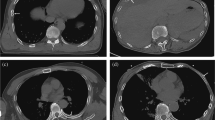

To collect data for constructing the CNN-based rib fracture detection model, the radiologists marked the fractures on the graphs. One radiologist marked the fracture sites on 1080 radiographs with the following signs: (1) complete rip disruption with a lucent line, (2) disruption of the inner or outer cortex, (3) fracture rib end displacement and (4) rib deformity with callus formation. To reduce the mark error, another radiologist confirmed all markers. As shown in Fig. 2, the training set contains 912 of the 1080 radiographs containing rib fractures, and the testing set contains 168 of the 1080 radiographs containing rib fractures and 233 radiographs not containing rib fractures. An additional validation set contains 201 chest radiographs collected from different period, 121 of which have rib fractures and 80 of which have not, and the validation set was confirmed by the same three radiologists with more than 15 years of radiological experience. One junior radiologist with 5 years of experience and one senior radiologist with 10 years of experience were also recruited for the rib fracture reading experiment.

Radiograph preprocessing, based on the multiscale image contrast amplification (MUSICA) algorithm. a The MUSICA algorithm diagram with picture resolve, high-frequency enhancer, and image reconstruction. b Two radiographs from different machines. c The corresponding graphs processed by MUSICA. Compared to the raw data, the processed graphs have a more consistent image quality, especially the rib display. d Variance of the signal-to-noise ratio (SNR) of the images before and after MUSICA processing

After MUSICA, the contrast uniformity between the bone and lung tissues was significantly improved (Fig. 3). Although the raw images behaved differently with considerable differentiation of contrast and detail, the two processed images appeared to be similar in image quality and contrast.